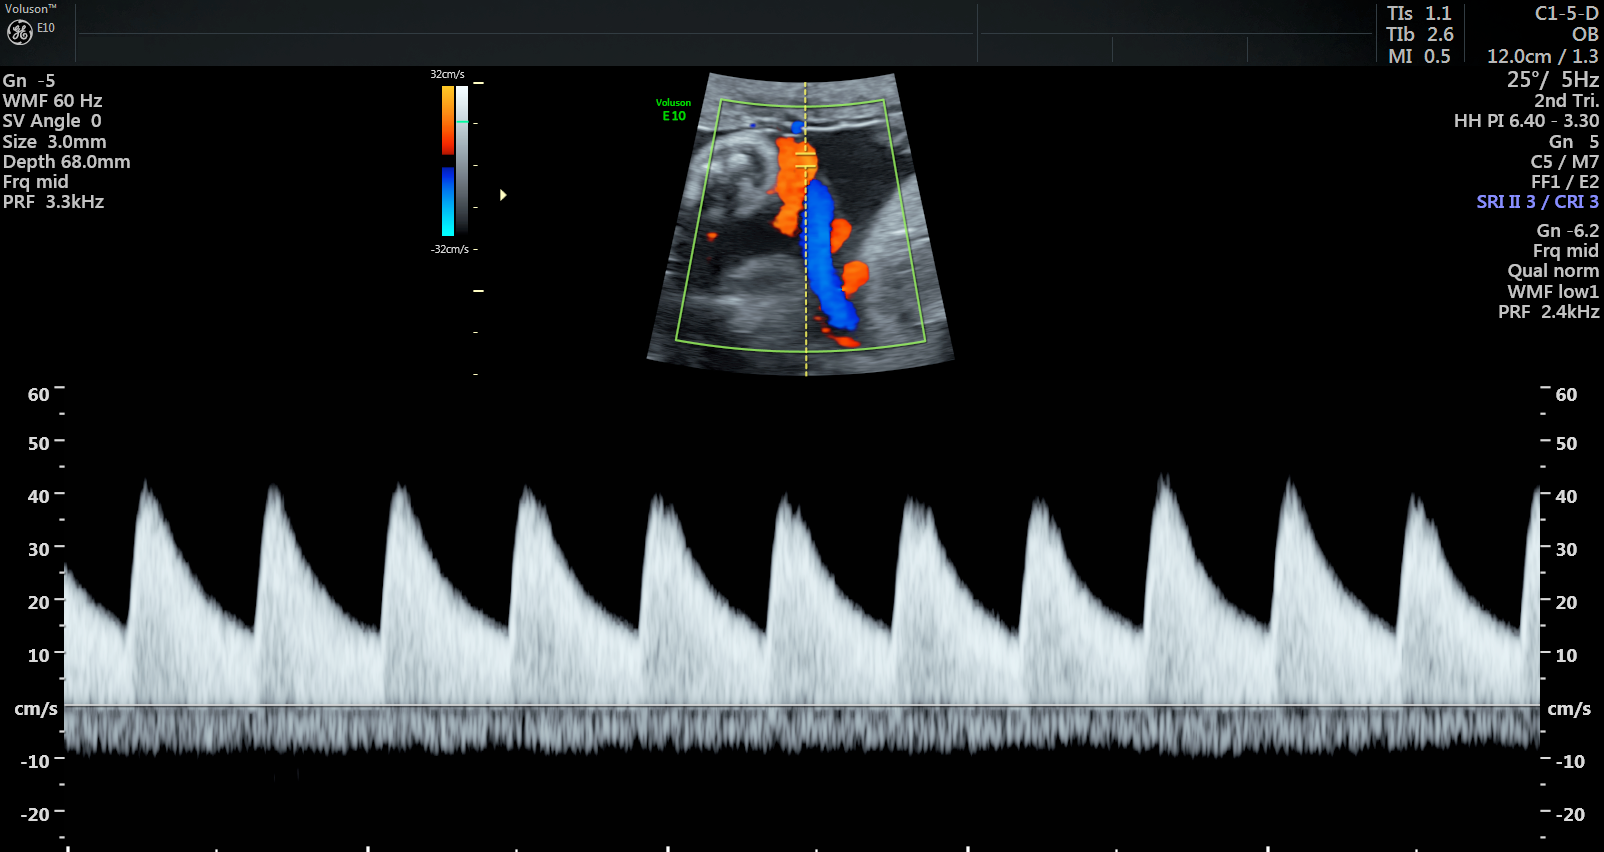

Currently, standard-of-care ultrasound scans measure blood flow at one point in the umbilical cord. The technique developed by Sled and his collaborators takes two measurements – one at the fetal end of the umbilical cord and one at the placental end. Sled says recording both measurements gives a much more accurate picture of the way blood is travelling through the umbilical cord.

“By looking at both measurements and the physics of how blood travels, we can get insight into how some of the finest blood vessels in the placenta are organized. The information this can provide to physicians is invaluable,” says Sled, who is also the Director of the Mouse Imaging Centre and a Professor and Vice-Chair in the Department of Medical Biophysics at the University of Toronto.

The placenta has two blood circulations, one attached to the mother and another attached to the fetus. If the disease is primarily affecting the maternal circulation, it’s called maternal vascular malperfusion (MVM) and if the fetal circulation is primarily affected, it’s called fetal vascular malperfusion (FVM). MVM is the most common placental disease associated with fetal growth restriction, where a fetus is smaller than expected, and is often the cause of preventable stillbirth. FVM is less common but also associated with fetal growth restriction and other adverse outcomes.